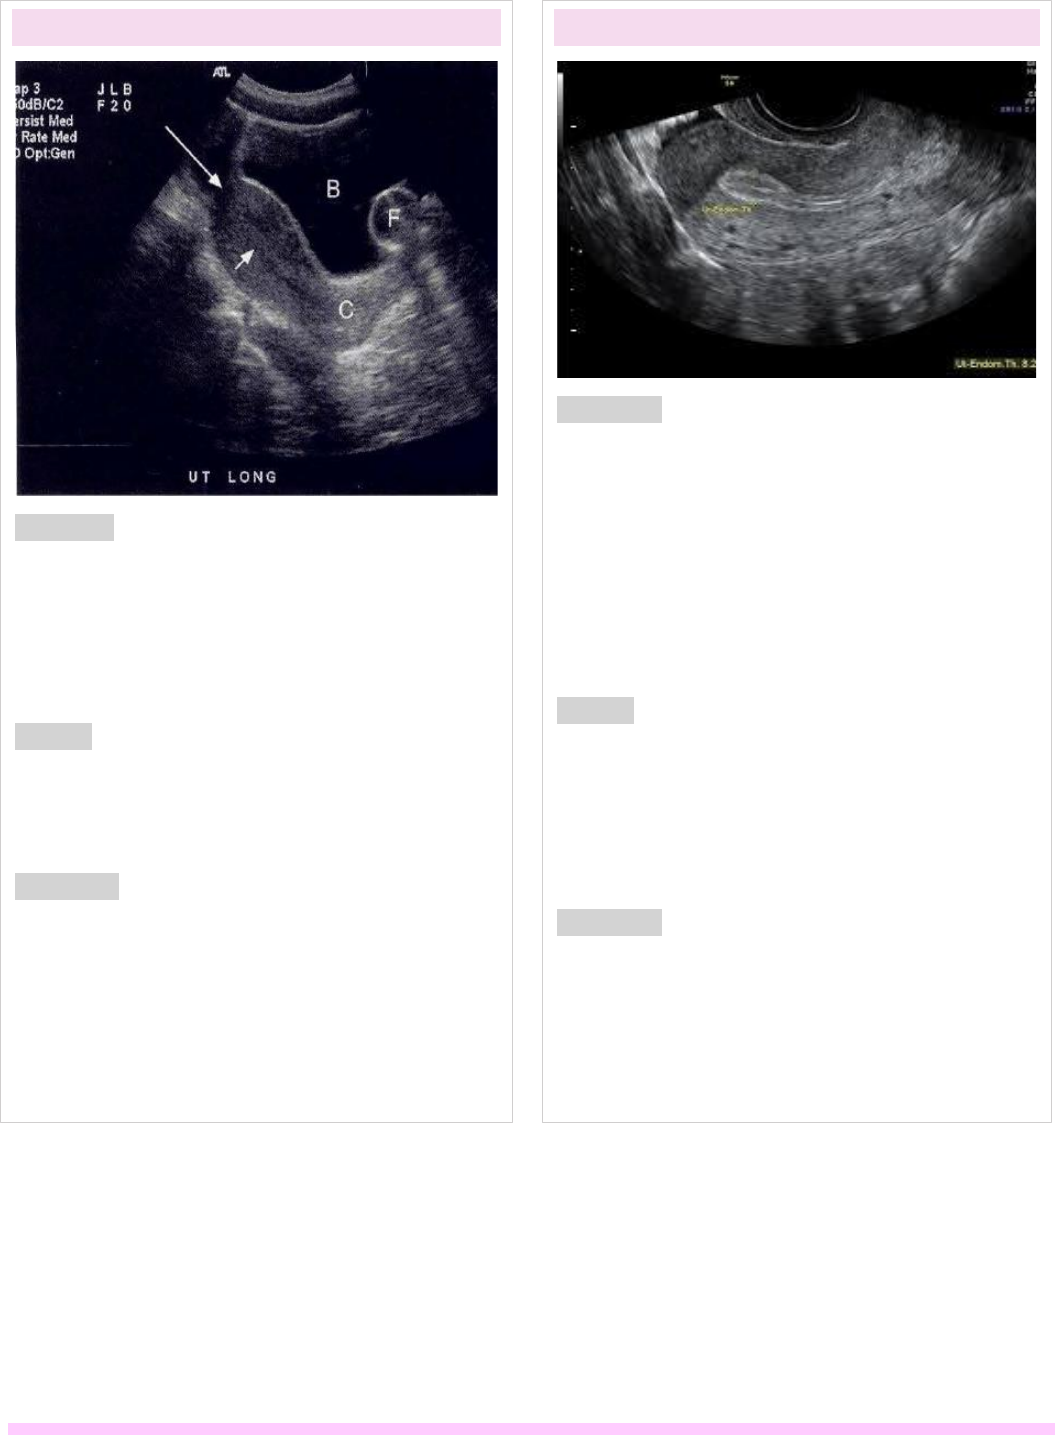

Slideshow endométrio heterogêneo o que significa

Endométrio heterogêneo